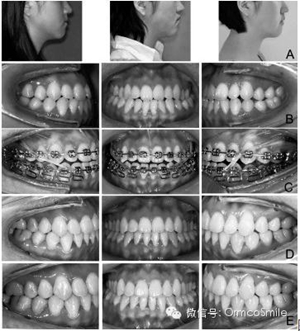

圖1 實(shí)驗(yàn)組患者示例。

A 治療前、治療結(jié)束、保持一年后的側(cè)貌;

B 治療前口內(nèi)像;

C 治療中口內(nèi)像;

D治療結(jié)束時口內(nèi)像;E保持一年后的口內(nèi)像